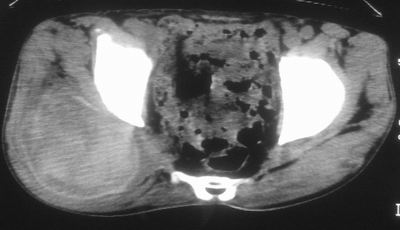

标题: CT16837:M63Y,右臀部巨大软组织包块 [打印本页]

标题: CT16837:M63Y,右臀部巨大软组织包块

患者,男,63岁,自诉3个月前发现右臀部包块,触及疼痛,治疗后缩小。前天突然增大。无高热病史。

考虑-----右臀大肌,臀中肌---感染性病变可能性大。

给个骨窗,判断一下肿块是否与髂骨有关,肿块内出血是肯定的,至于是感染形成的脓肿还是起源于肌肉或纤维组织的肉瘤则难以确定,不过从影像上看,包膜完整,且环形增厚,病灶下部见斑片状底密度坏死,个人倾向感染可能性大

肌间隙明显混浊,三个月前治疗有缩小,支持考虑臀大肌下脓肿伴出血,肿瘤如果出现瘤内出血的话瘤外边界应该较清楚,现在表现为一种恶性征像,但骨质无明显异常,且臀小肌边界清楚,不符合恶性表现.